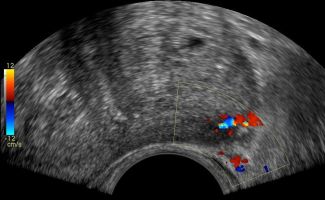

- Peripheral Prostate Zone: The exam can detect focal lesions, such as neoplasms, in the peripheral zone of the prostate.

- Central Prostate Zone: The central zone can be checked for the presence of inflammation, abscesses, calcifications, or other space-occupying lesions.

The Transrectal Ultrasound provides more information about the size, morphology, and focal lesions of the prostate compared to the lower abdominal ultrasound. As a specialized examination, it is performed when there are clinical and biochemical indications, such as elevated PSA (prostate-specific antigen).